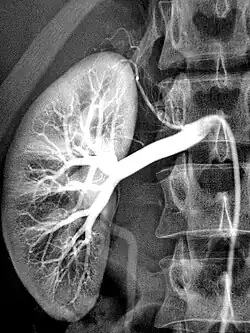

Arteriografie einer gesunden Niere

Die Wirkung von Kontrastmitteln besteht darin, das Signal, welches in der jeweiligen Untersuchung registriert wird, zu modifizieren. Ziel des Einsatzes ist, bei der Untersuchung Zusatzinformationen zu gewinnen. So kann man bei Röntgenaufnahmen Kontrastmittel verwenden, die Röntgenstrahlen stärker absorbieren als normales Weichteilgewebe. Gewöhnlich sieht man auf einem Röntgenbild beispielsweise keine Blutgefäße. Wenn man eine iodhaltige Lösung injiziert, werfen die Gefäße, in die die Lösung gelangt, Röntgenschatten und werden so sichtbar (Angiografie).

• Bereits etwa 1923 wurde zur Röntgendiagnostik beispielsweise der Gallenblase das von Evarts A. Graham eingeführte Tetrajodphenolphthalein und ab 1940 das von Max Dohrn und Paul Diedrich entwickelte und besser verträgliche Biliselektan verwendet. Seit 1953 werden auf Hedwig Langecker zurückgehende trijodierte Kontrastmittel angewendet.[12] Iodhaltige Kontrastmittel sind wasserlösliche Substanzen, die entweder intravaskulär gespritzt oder direkt in das darzustellende Gewebe/Hohlorgan injiziert werden. Sie werden zu über 90 % über die Nieren ausgeschieden. Sie dienen zur Darstellung der Nieren und Harnwege (Urografie/Ausscheidungsurografie), der Venen (Phlebografie), der Arterien (Arteriografie) oder anderer Organe. Die verschiedenen iodhaltigen Kontrastmittel unterscheiden sich vor allem in den Trägermolekülen, in der Zahl der pro Trägermolekül gebundenen Iodatome (1 bis 6) und in ihren physiko-chemischen Eigenschaften (Osmolalität, Viskosität, Hydrophilie). Von der Iodkonzentration hängt die Röntgendichte und damit die erreichbare Kontraststeigerung ab. Die Osmolarität beeinflusst (teilweise) die Verträglichkeit des Kontrastmittels, während die Viskosität seine Fließeigenschaft (durch Katheter oder auch beim Spritzen) bestimmt. Mögliche Risiken iodhaltiger Kontrastmittel sind unter anderem Hyperthyreosen.